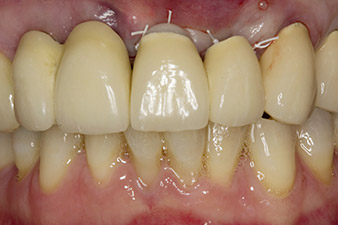

initial radiological findings

Fig. 1: The initial radiological findings revealed a splinted crown restoration requiring replacement. When the restoration was removed, teeth 21 and 22 were unintentionally extracted along with it.

The x-ray revealed horizontal bone loss around teeth 21 and 22 (Fig. 1). When the crown block was removed, these teeth were unintentionally extracted with it.